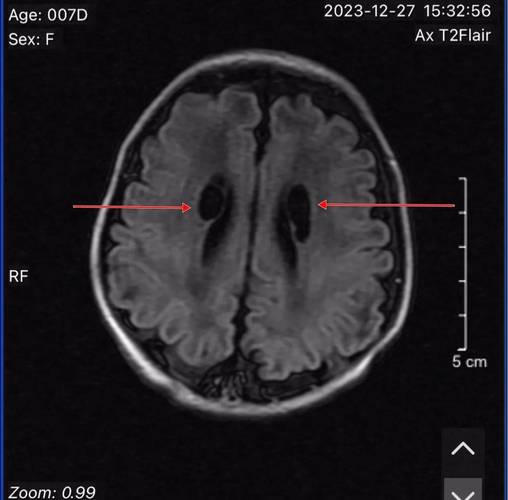

- CT表现:脑白质,特别是侧脑室周围的白质,会出现弥漫性或片状的密度降低,严重时,脑沟可能变浅,脑室可能扩大,这是脑水肿的表现。

脑白质软化

- 原因:主要发生在早产儿,与脑室周围白质区域的缺血和炎症反应有关。

- CT表现:早期表现为脑白质低密度,后期(数周或数月后)可能会形成囊腔或脑室扩大(脑室周围白质软化后遗症)。

- 其他检查:是否有头颅B超(对新生儿更常用,无辐射)、MRI(磁共振,对脑白质显示更清晰)的结果?这些比CT更有价值。

- CT vs. MRI:对于新生儿脑部评估,MRI是金标准,CT虽然快速、方便,但对脑白质的细微结构和早期病变的分辨能力不如MRI,且有辐射,医生可能会建议在宝宝情况稳定后,做一个头颅MRI来更准确地评估脑损伤的范围和性质。